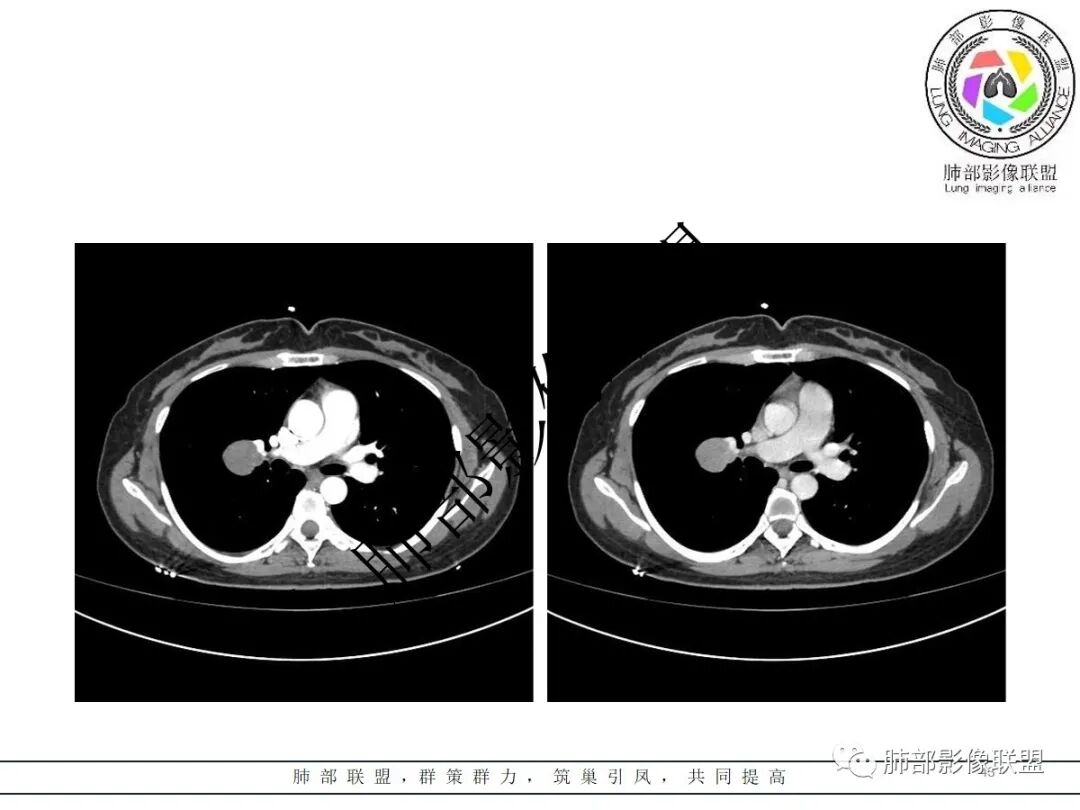

右肺门类圆形实性肿块,边缘光滑,无分叶毛刺,跨叶,推移血管,密度均匀,增强延迟强化相对明显,未见坏死及血管造影征。

2.右肺水平叶裂斜叶裂肺门交界区类椭圆形块影,表面光整,未见分叶毛刺及棘状突起,未见邻近结构牵拉。与邻近支气管无关联。

3.病灶密度均匀,未见液化坏死、钙化及脂肪低密度。轻度强化,可见纤细血管影蜿蜒穿行。右肺动脉推移变形,未见侵入或充盈缺损。

4.灶周未见磨玻璃晕或极低密度影环绕。右肺下叶背段胸膜下见微小实性密度结节影,边界清楚。

5.双肺门及纵隔未见增大淋巴结。双侧胸腔未见积液。